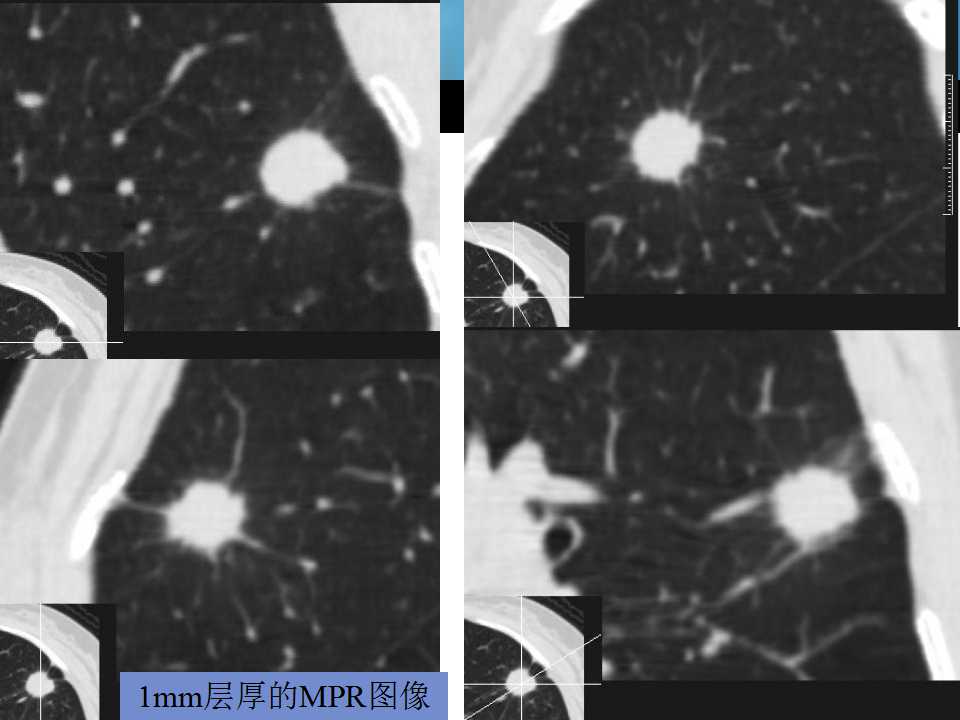

肺癌影像诊断